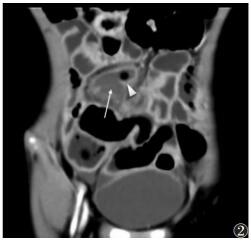

① 9例急性单纯性阑尾炎,MSCT示阑尾管腔均增宽,外径6~9 mm,管腔内多伴少许积液,管壁增厚不明显,管壁边缘及周围脂肪间隙密度模糊,表现为细网线状略高密度影;7例粪石均可显示(图 1),MSCT表现为直径为25 mm的点状或小类圆形高密度影,多位于阑尾根部;伴盆腔积液2例,回盲部周围淋巴结肿大1例。②19例急性化脓性阑尾炎,MSCT示阑尾管腔均增宽,外径8~14 mm;12例伴高密度粪石,当圆形高密度粪石嵌顿在阑尾根部,远端管腔因阻塞常增宽明显;阑尾管壁肿胀,厚度>3 mm,边缘模糊不清,管腔内多伴积液及气泡,6例管腔周围伴脓肿形成,CT表现为高于水样密度影,可伴气泡;4例阑尾脓肿伴穿孔MSCT示2例阑尾局部管壁连续性中断(图 2);5例肠淤张,表现为腹盆部小肠呈不同程度扩张,肠管拥挤,管腔内积气积液;伴盆腔积液14例,肠系膜周围淋巴结肿大2例。③16例急性坏疽性阑尾炎,MSCT示阑尾管腔不同程度扩张,外径7~18 mm,管壁明显增厚(图 3);4例局部管壁连续性中断,管腔周围可伴脓肿及气泡;14例管腔内伴圆形高密度粪石,管腔内积气、积液;9例管壁周围脂肪密度可见条状、片状增高,邻近回肠末端及盲肠管壁增厚;6例肠淤张;伴腹盆腔积液10例,肠系膜淋巴结肿大4例。

| 图 2 男,8岁,急性化脓性阑尾炎伴穿孔,阑尾外径明显增宽,达12.5 mm,管腔积气积液(三角),管壁下缘局部不连,周围积脓(长箭),盆腔少量积液 |